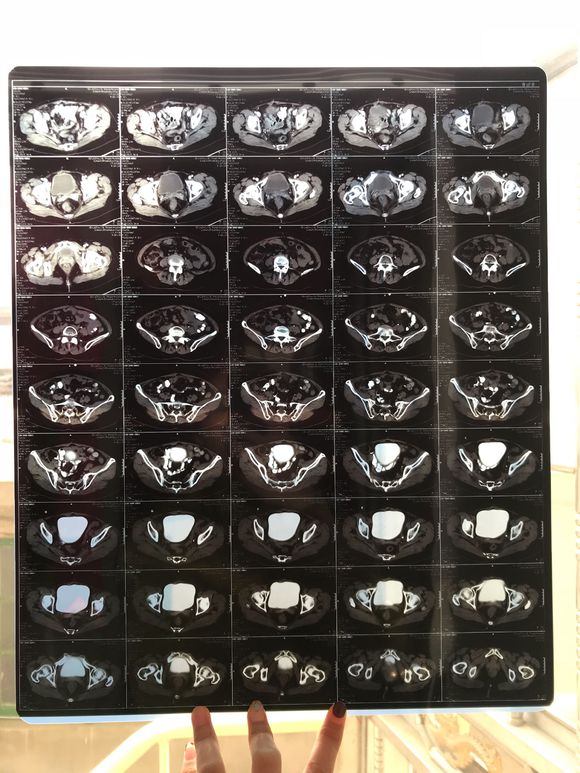

和你的故事 02019-04-09 患者家属我妈妈的病理结果报告,3期c1,大家可以帮忙看看吗,跪求了!我很急,谢谢!想知道是否严重,目前等术后出院后去肿瘤医院...

0人关注 4个回复 3468次浏览 -